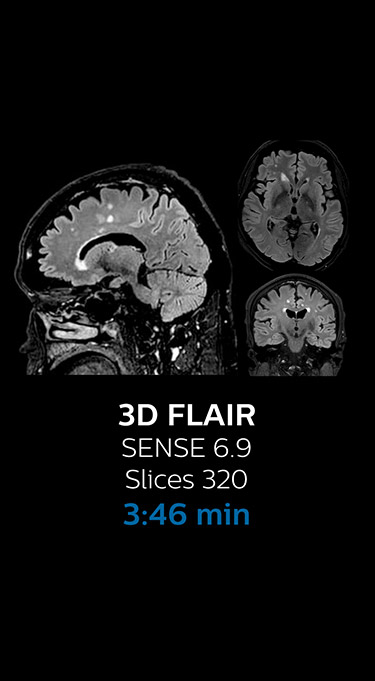

“We now only need about 10 minutes of scan time for a brain exam – and we still get the same amount of images and equal quality. We even managed to make a very useful improvement: we replaced the 43-second T21 FFE by a 43-second SWIp, which is more powerful for us in making confident diagnoses in certain patients.” “SWIp was not previously included in our standard protocol, because of its slightly longer scan time. SWIp provides high resolution 3D susceptibility weighted imaging in the brain, which helps to visualize small deoxygenated blood or calcium deposits. Now, with Compressed SENSE, we can perform 3D SWIp in only 43 seconds, so we have included SWIp instead of the 2D T21 FFE that we used previously. Without adding scan time, we now get SWIp images in every routine brain scan and it helps us increase our diagnostic confidence in certain cases.”

The most frequently used brain MRI examination at KNC included approximately 15 minutes of scanning time, and was quite comprehensive with fairly short scan times. When Compressed SENSE became available, its great impact on the brain exam quickly became clear.

Fast MRI of brain

With Compressed SENSE, the scan time for the routine brain examination at KNC was reduced from 15:48 to 10:19 minutes, which corresponds to 35% reduction.

Ingenia 3.0T CX

Scan time 15:48 min.

Brain with Compressed SENSE

Ingenia 3.0T CX

Scan time 10:19 min.